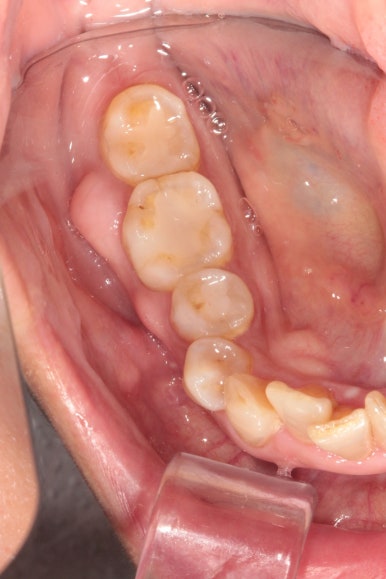

위에 보이는 사진은 교정장치를 붙이고 불과 4개월 후 입니다!

생각보다 위턱 앞니가 빨리 가지런해 진 것을 확인할 수 있습니다.

아래 앞니만 조금 더 가지런해지면... 될 것 같은 느낌이네요.

그리고 교합면 사진을 통해 전체적인 진행 상태도 파악할 수 있죠.